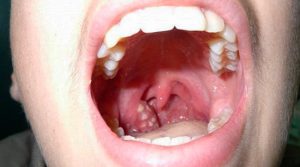

Amigdalite crônica é quando suas amígdalas inflamam repetidamente. Elas ficam inchadas, vermelhas e podem doer bastante. É uma condição chata que atrapalha o dia a dia, viu?

A amigdalite crônica acontece quando as amígdalas, aquelas “bolinhas” na parte de trás da garganta, ficam inflamadas por um longo período. Elas podem acumular bactérias e restos de comida, se tornando um foco de infecção. Essa inflamação constante pode te deixar com a garganta irritada o tempo todo, um incômodo que atrapalha a fala, a alimentação e até o sono. Se você sente esses sintomas com frequência, não demore para procurar um médico.